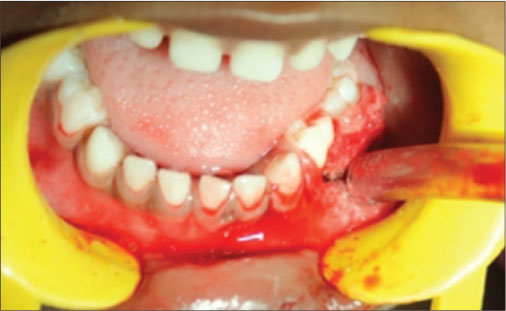

A 4-year-old female patient came with a complaint of growth in the lower back tooth region of lower jaw for 1 week. Parents of the patient noticed the growth a week back which was smaller in size initially which increased suddenly to the present size. Growth was not associated with pain or any other symptoms initially but later developed discomfort while eating associated with mild pain. The patient was given anti-inflammatory medication for the relief of pain and swelling for about 3 days, but there was no reduction in size of the growth. Medical and family histories were noncontributory. On extraoral examination, fullness is seen on the left lower third of face. A solitary left submandibular lymph node enlargement is felt, which is freely movable and tender. Intraorally, an exophytic growth was seen arising from gingiva in relation to 73, 74, and 75 tooth region [Figure 1] measured approximately around size 2 cm × 3 cm, slight pale in color with pinpoint erythematous areas. This appeared to be covered by keratotic surface and seemed to have papillary projections. On palpation, the lesion was pedunculated fibrous inconsistency, nontender, and slight bleeding on provocation, and diascopy test was negative. Considering the patient’s history and clinical examination, a provisional differential diagnosis was arrived which is as follows PG, verrucous hyperplasia, hemangioma, peripheral giant-cell granuloma, peripheral ossifying fibroma, fibroma, and peripheral odontogenic fibroma. The following sets of radiographs were advised to rule out any bony involvement. Intraoral periapical radiograph (IOPA) and occlusal radiographs showed soft-tissue shadow with respect to 73, 74, and 75 [Figure 2] and [3]. Later, complete blood picture was done which did not show any variations from the normal limits. The lesion was subjected for excisional biopsy under local anesthesia [Figure 4] and [5] and subjected to histopathological examination which revealed to be angiomatous granuloma [Figure 6] and [7]. The patient was followed up for 1 year after surgery and there was no evidence of recurrence.

| Figure. 1 Exophytic growth was seen arising from gingiva in relation to 73, 74, and 75 tooth region